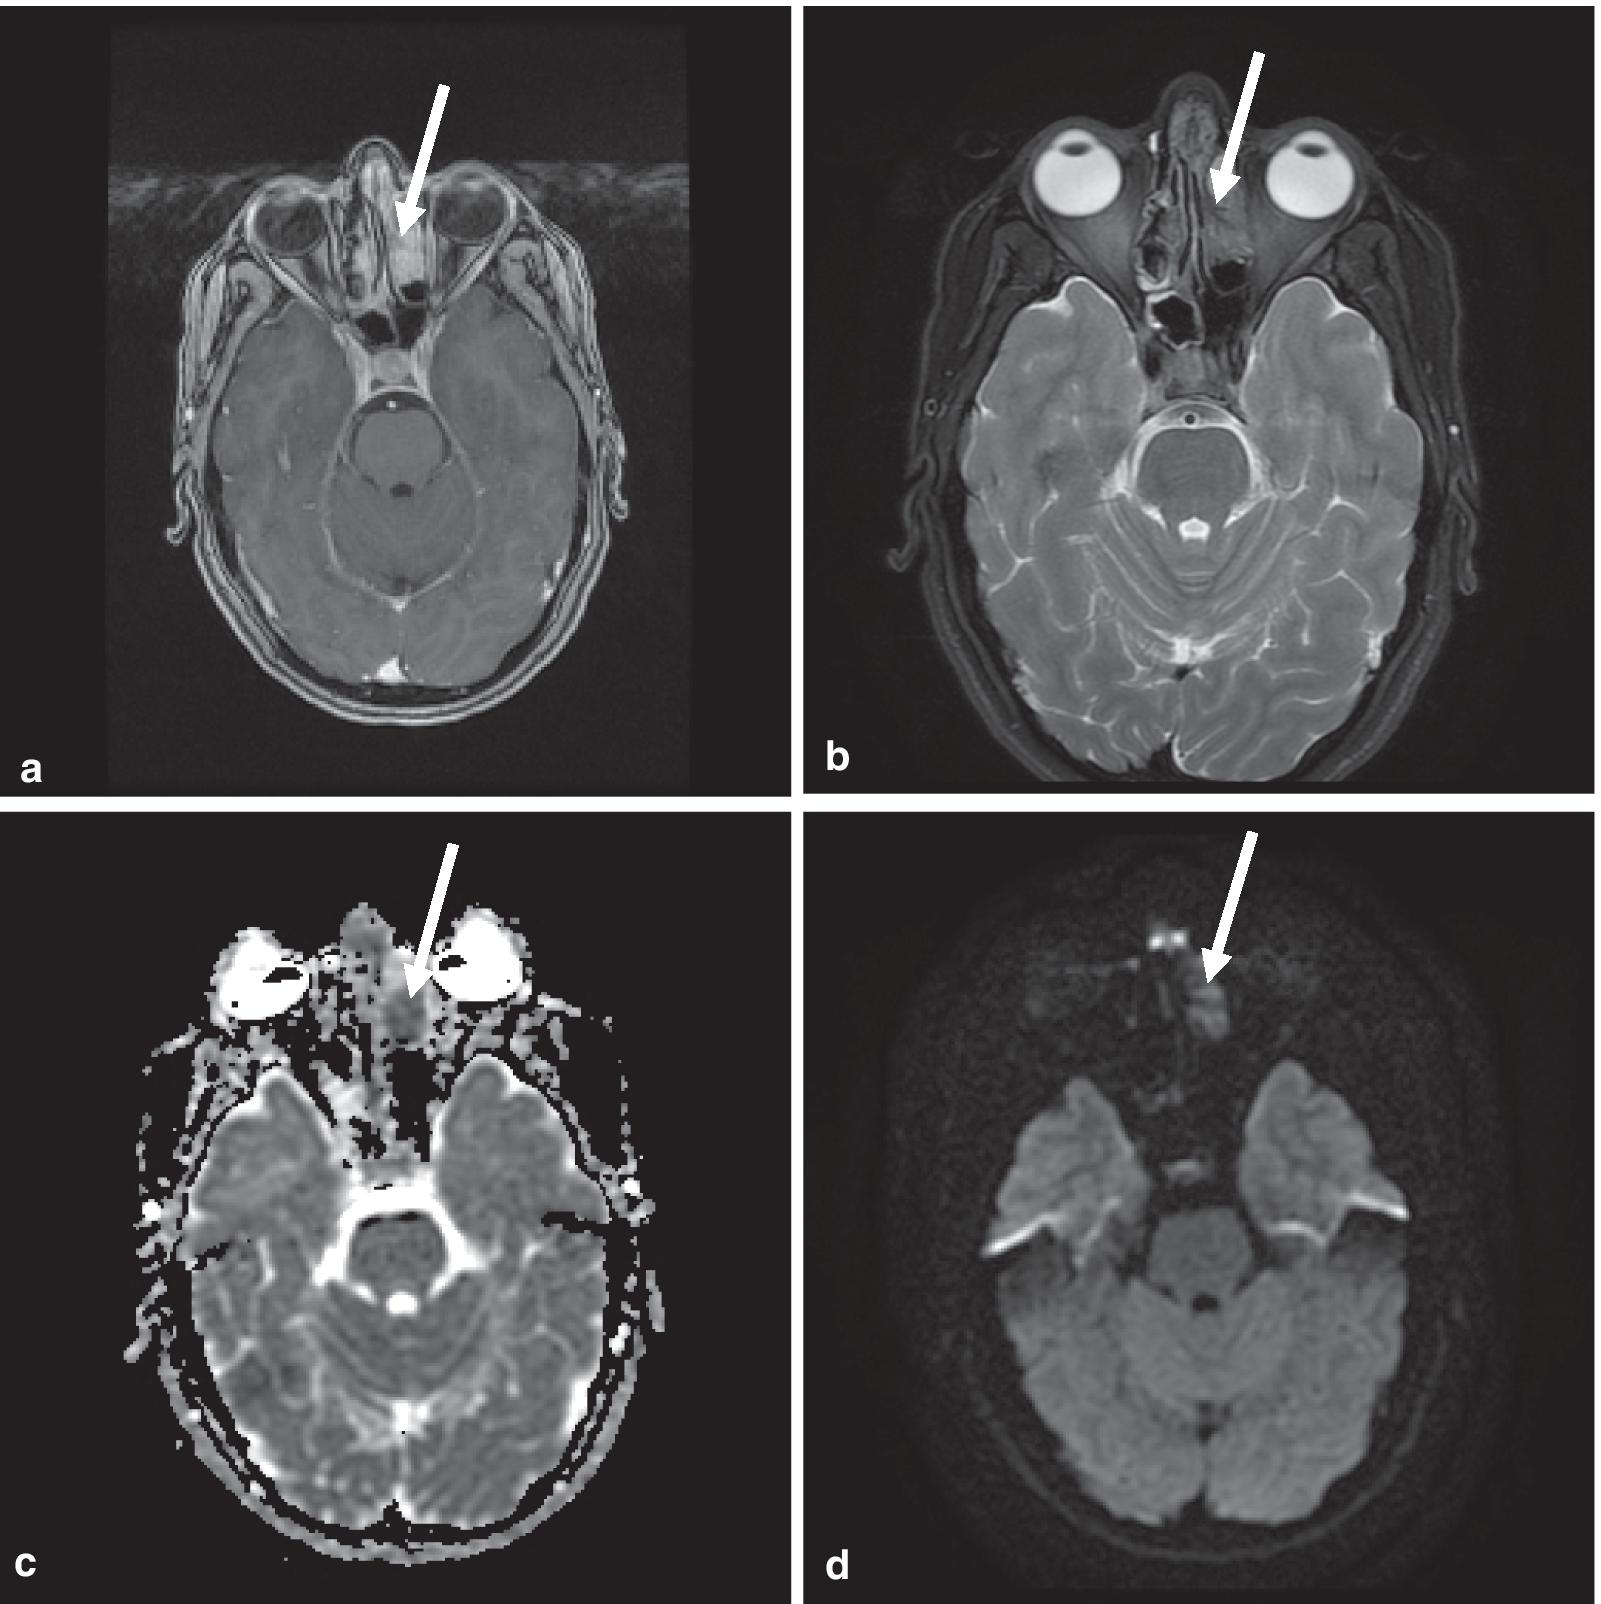

Fig. 1

Contrast-enhanced maxillofacial MRI demonstrates left ethmoid sinus lesion. a Enhancing infiltrative lesion in the left anterior ethmoidal sinus in the Gadolinium-enhanced sequence (White arrow). b This lesion is hypointense in the T2-weighted sequence. c, d The lesion is hypointense in the apparent diffusion coefficient (ADC) sequence and mildly hyperintense in the diffusion-weighted imaging (DWI) sequence, likely due to hypercellularity